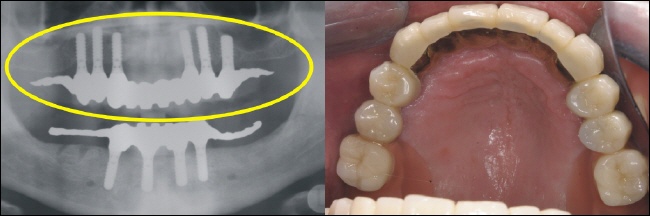

Sechs strategisch günstig positionierte Implantate wurden im Oberkiefer eingebracht, um nach der Einheilung optimalen Halt für die Prothese zu gewährleisten (gelber Kreis im Röntgenbild). |

Im Unterkiefer können die vier Implantate (Standardversorgung) im vorderen Kieferbereich eingebracht werden (gelber Kreis im Röntgenbild). |